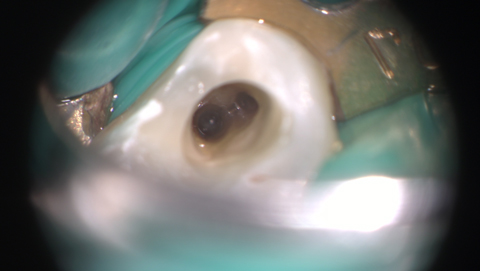

投稿日: 2018年2月14日2018年10月31日 投稿者: 木田歯科医院下顎4番2根管 下顎4番は普通は1根管の歯ですが、このところ2根管が2回連続です。 入り口の直径は最初は0.08ミリがやっと通る程度です。 ある程度拡大したところ。 でもいちばん大事なのは根管内に細菌を入れないことです。